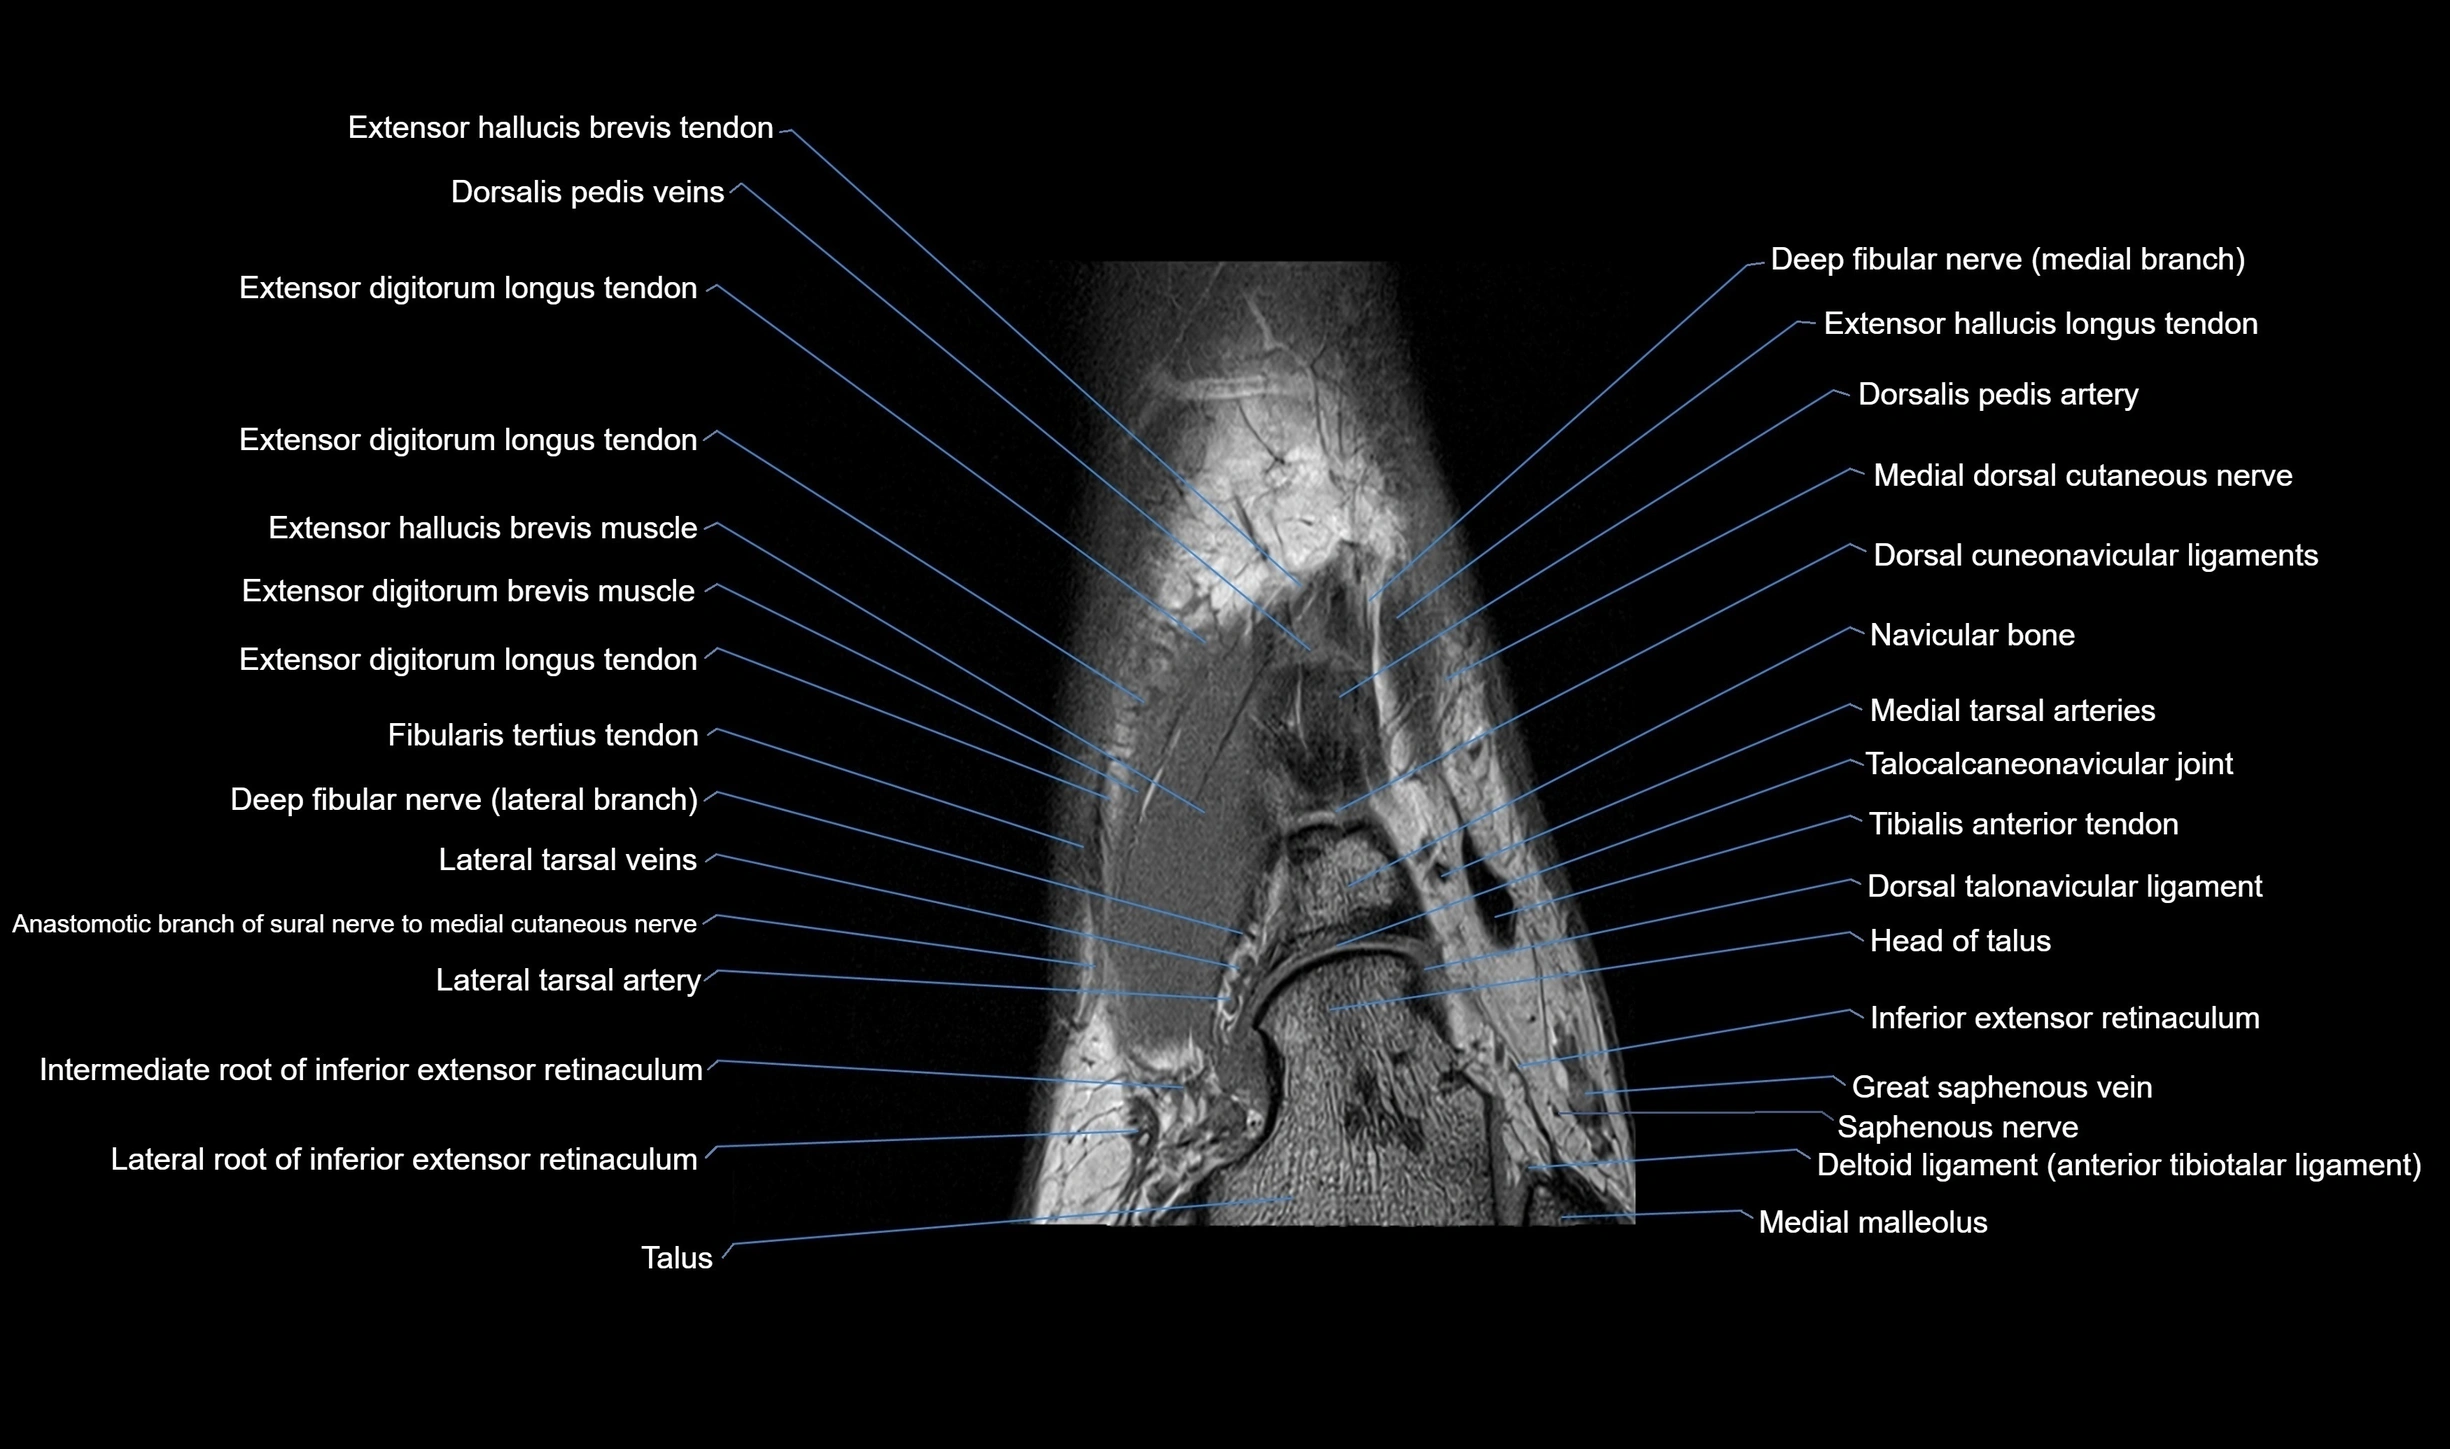

MRI image